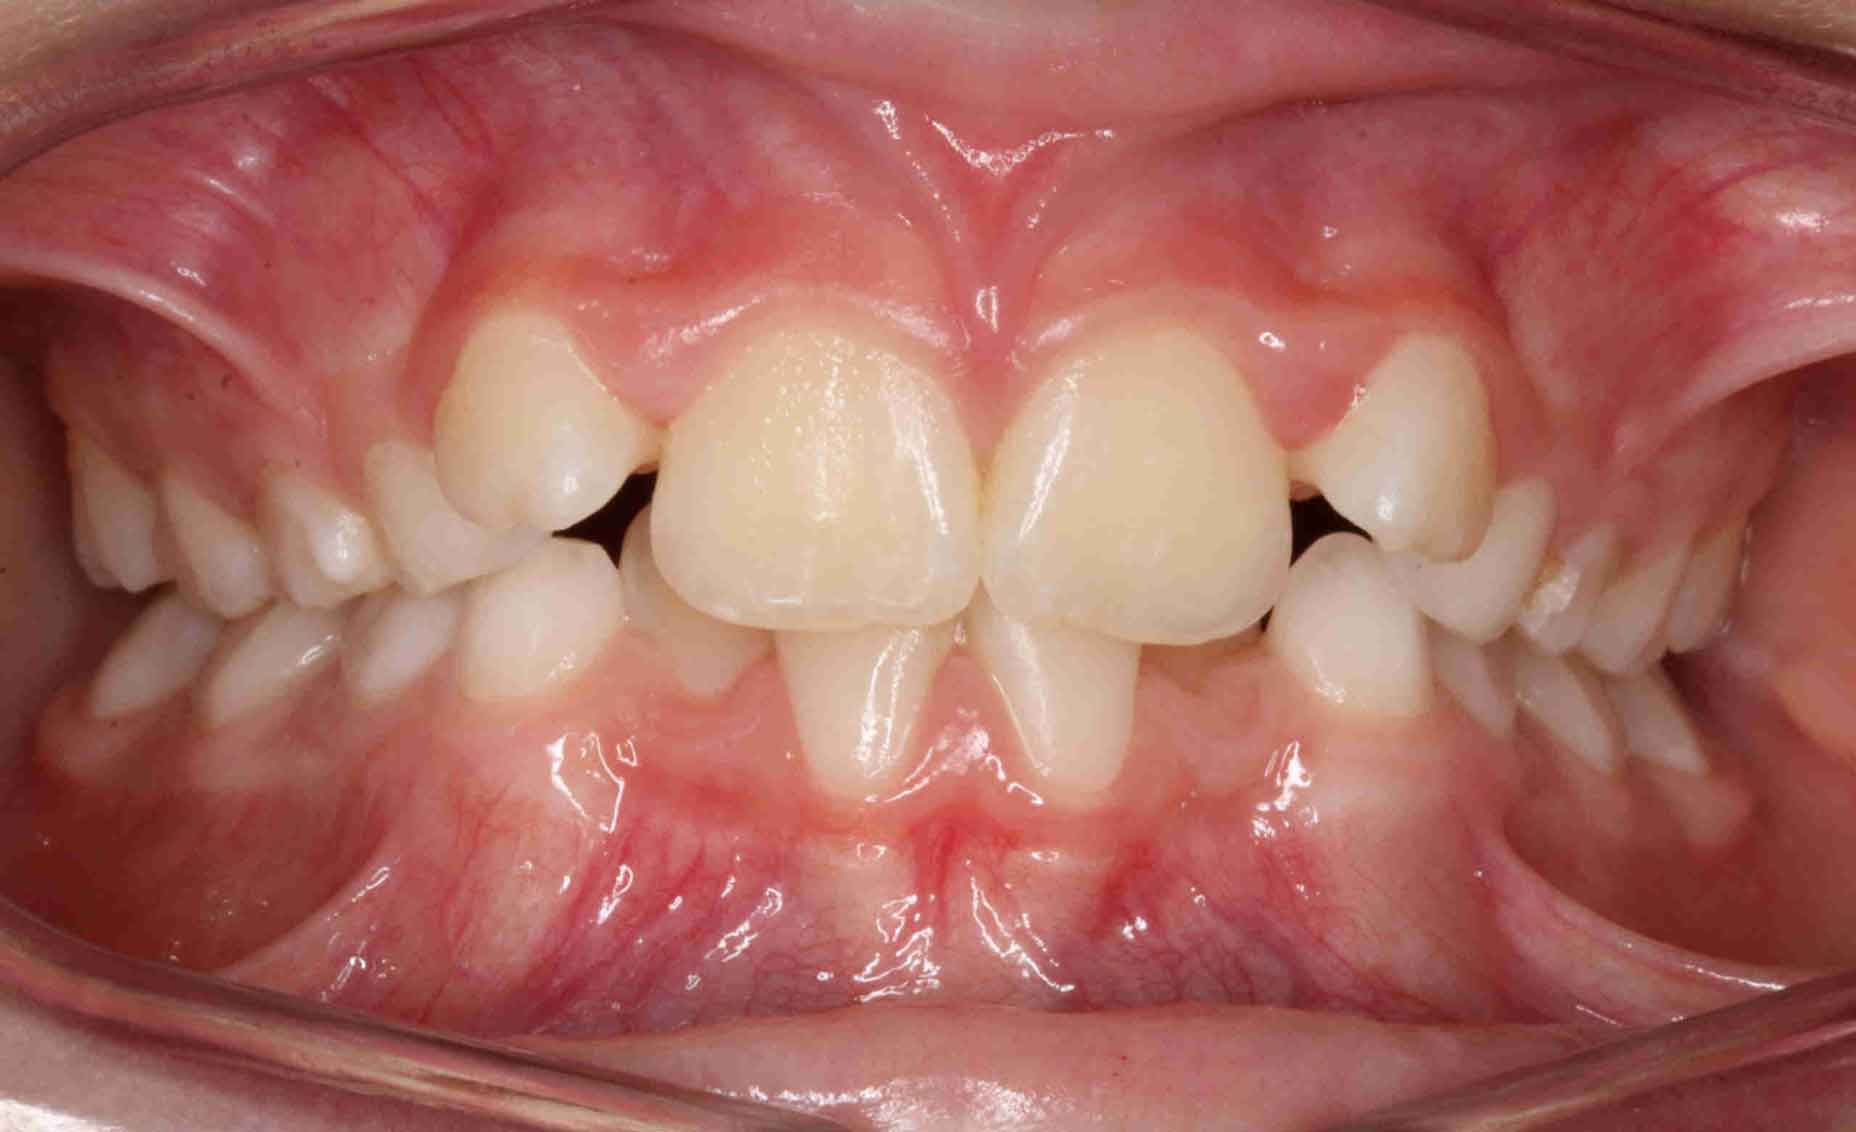

Caninos Impactados

En las siguientes imágenes puedes ver distintos resultados del tratamiento, deslizando la barra central de un lado a otro.